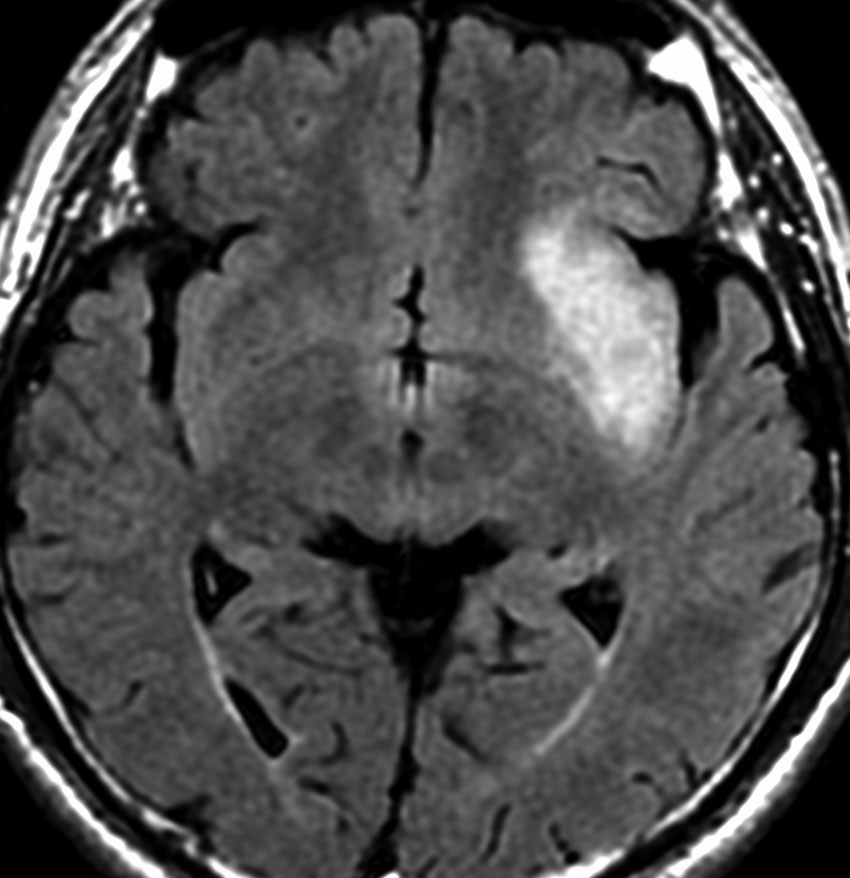

若い女性の左前頭葉から島回,側頭葉を侵す腫瘍で,てんかん発作で発症し,開頭生検 biopsy しました。

一部で,細胞密度が高く,核の腫大とクロマチンの増量,核間距離の短縮があり,核分裂像が認められ,MIB-1染色率が10%です。組織学的には退形成性乏突起膠腫グレード3とされました。

IDH変異あり,1P/19q欠失あり,ATRX変異なしです。

乏突起膠細胞系グリオーマなので,放射線治療の高線量領域はあまり広くとりません。

IMRT Simultaneous Integrated Boost (SIB)で,FLAIR高信号の領域に54グレイ27分割,周囲仮定浸潤領域 generous local areaに46グレイを照射しました。

テモゾロマイド75mg/m2を併用しています。

左の画像は放射線治療直後のMRIですが,すでに腫瘍の縮小がみられます。

テモゾロマイドの維持療法は,24コース 2年間行い,それ以降は無治療としました。

照射後7年の画像です。腫瘍は縮小したまま,患者さんは無症状で経過しています。